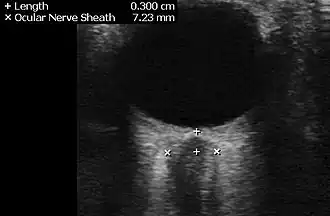

Neuroimaging, usually with computed tomography (CT/CAT) or magnetic resonance imaging (MRI), is used to exclude any mass lesions. In IIH these scans typically appear to be normal, although small or slit-like ventricles, dilatation and buckling[18] of the optic nerve sheaths and "empty sella sign" (flattening of the pituitary gland due to increased pressure) and enlargement of Meckel's caves may be seen.

An MR venogram is also performed in most cases to exclude the possibility of venous sinus stenosis/obstruction or cerebral venous sinus thrombosis.[5][7][8] A contrast-enhanced MRV (ATECO) scan has a high detection rate for abnormal transverse sinus stenoses.[15] These stenoses can be more adequately identified and assessed with catheter cerebral venography and manometry.[16] Buckling of the bilateral optic nerves with increased perineural fluid is also often noted on MRI imaging.